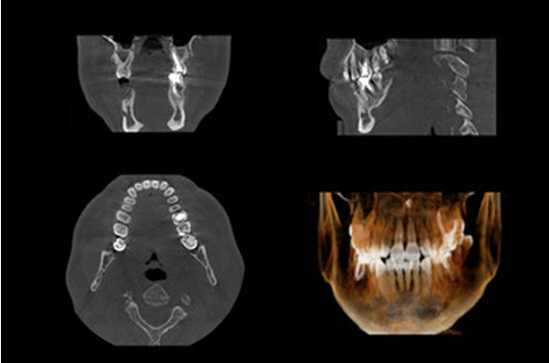

歯科用コーンビームCT

3D立体映像で口腔構造を可視化し、インプラント体を支える顎骨を診断します。骨の長幅径、上顎洞、下顎洞の距離を計測し、安全にインプラント手術を進められるように検査を行います。